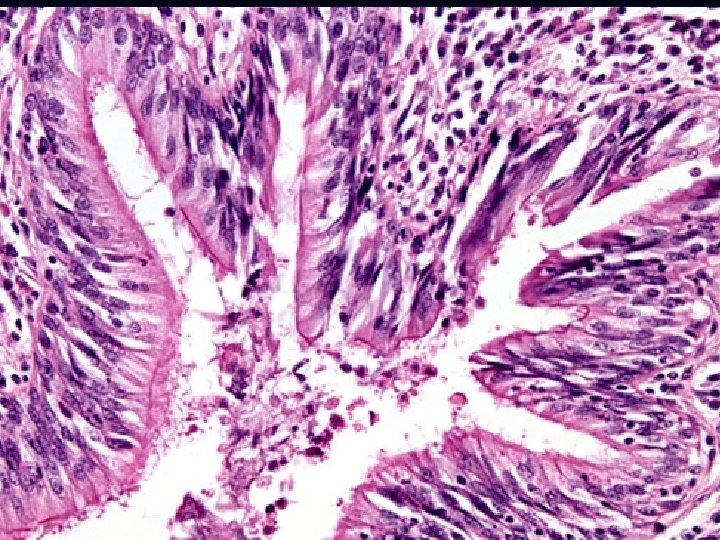

Basic Mechanism: : n Hypersecretion of mucus n Histology -Increased numbers of goblet cells in small airways as well as large airways. -Increased size of submucosal glands in large airways (Reid index: ratio of thickness of mucosal glands to thickness of wall between epithelium and cartilage) -Peribronchiolar chronic inflammation.

n Histology: -Thick basement membrane -Edema and infiltration of the bronchial walls by inflammatory cells with prominence eosinophils, - Hypertrophy of bronchial wall muscle. of